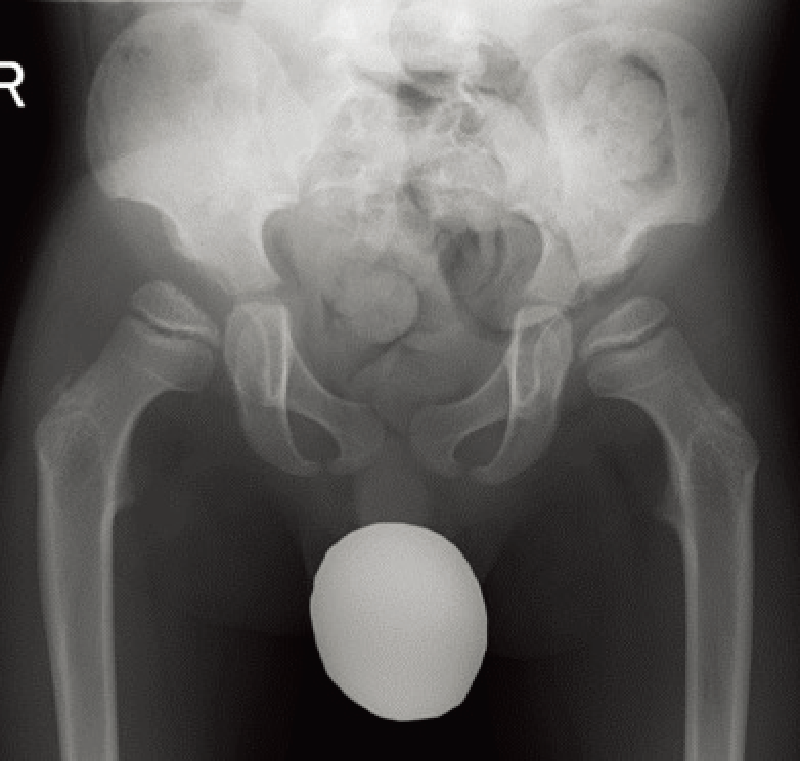

罹患症例の10~20%は両側性。両側性に発症する場合、通常は左右非対称で、異なる病期に発見される(A)。

特徴的な画像所見:初期には関節腔の拡大、大腿骨頭骨端部の骨硬化(B)、前外側の軟骨下骨折線(Crescent sign)を認める。後期は大腿骨頭の扁平化、分節化(A)などがみられる。

A. 両股関節正面像(年齢・性別不明):右は初期、左は進行期のペルテス病。